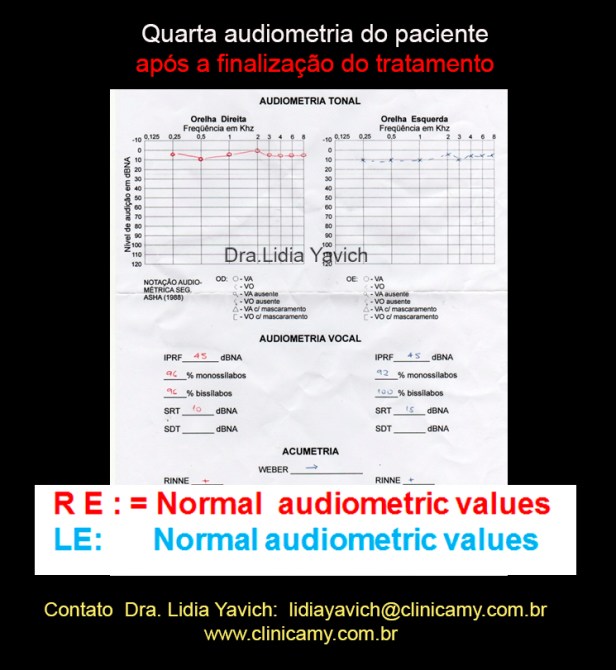

A quarta audiometria do paciente após a finalização das duas fases do tratamento mantém os limiares normais no ouvido esquerdo e limiares normais no ouvido direito.

Comparação da primeira, segunda, terceira e quarta audiometria do paciente.

Normalização dos limiares no ouvido esquerdo e no ouvido direito.